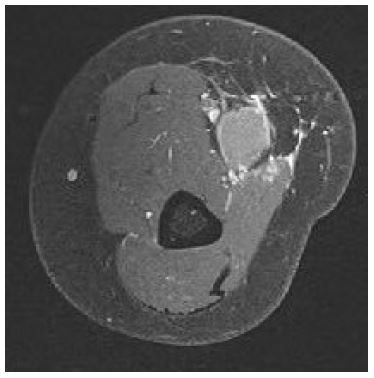

In January 2022, a 19-year-old pregnant female in her 36th week of pregnancy presented with a mass in the right forearm. The mass was investigated using Magnetic Resonance Imaging (MRI), the results of which are shown in Figures 1 and 2, revealing a suspicious lesion in the forearm flexor compartment. A subsequent biopsy was performed, and histopathological analysis confirmed the diagnosis of alveolar rhabdomyosarcoma as can be seen in Figure 3.

Figure 2: Axial diffuse weighted imaging through the patient’s right forearm demonstrating restricted intralesional diffusion, highlighting underlying hypercellularity.